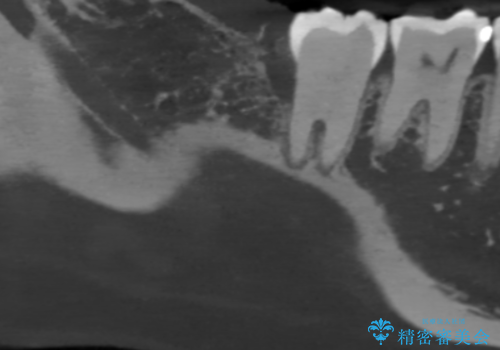

右下7番遠心に深い歯周ポケットが存在し、深い骨欠損も認めたため、放置・悪化すると歯の喪失につながるリスクを説明し、歯科衛生士による歯周病治療を挟んだ後再生療法を行いました。

来院時、右下7遠心9mm、舌側6mmと深い歯周ポケットを認めました。

遠心から舌側、唇側に及ぶ深い垂直的骨欠損も認めたため、歯科衛生士による歯周基本治療の後、歯周外科(再生療法)を行いました。

レントゲン写真は、処置後一年経過時のもので、歯周ポケットは遠心4mm、舌側3mmまで減少、出血なし。

一度目の再生療法でできる骨形態は移行的でないこともあるため、経過を診つつ骨整形も必要であれば今後行う予定です。